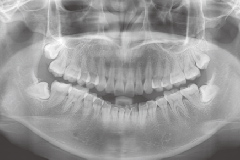

X片檢查

影像記錄

頭影測量

影像分(fēn)析